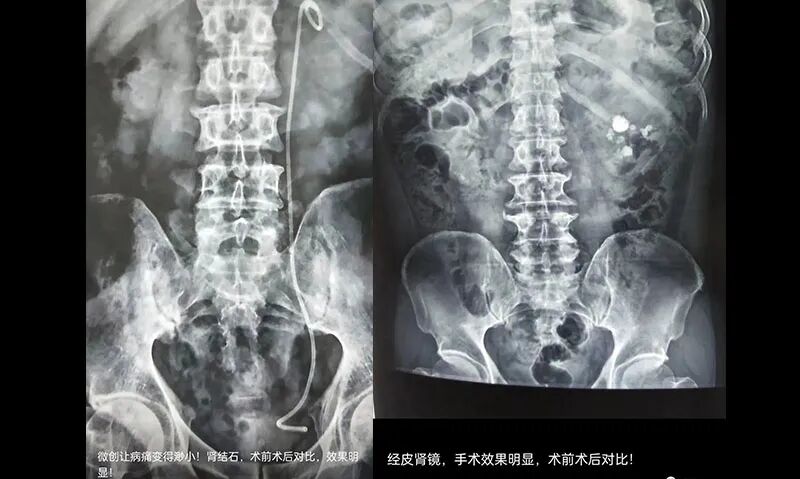

3. 對(duì)于直徑大于20mm的腎結(jié)石,或是L4水平以上,梗阻較重,直徑大于15mm的結(jié)石,或者輸尿管結(jié)石形成梗阻,長(zhǎng)期腎積水患者,需要根據(jù)結(jié)石的具體大小、位置、來(lái)決定是否行經(jīng)皮腎鏡碎石術(shù)或是經(jīng)尿道輸尿管軟鏡碎石術(shù)。